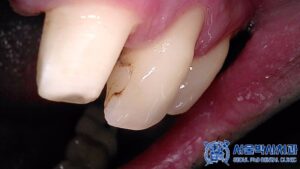

환자분의 경우, 앞니 양옆에 위치하고 있는 치아들이

여전히 구조적으로 유지가 가능한 상태였고,

무엇보다 가운데에 매복되어 있는 치아를

발치하지 않고도 치아의 기능을

회복할 수 있었기 때문에 임플란트 대신

브릿지 치료를 진행하기로 하셨습니다.

단 치아를 삭제한 후 크라운을 수복해야 하므로

치아가 시리지 않도록 신경치료를 진행하여

최대한 자연치아를 보존하기로 하였습니다.